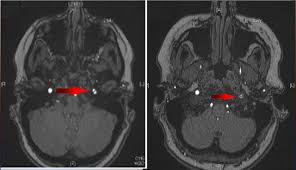

Carotid artery dissection (concept id: Each common carotid artery has an internal and an external branch. Carotid artery dissection is a tear in one of the layers of the artery wall. Spontaneous dissection of the carotid artery occurs in 3 per 100,000 of the population annually (1). It manifests with headache, neck pain, temporary vision loss, and/or ischemic stroke. This causes bleeding into the artery wall. Commonest in those in their mid 40s but seen at any age. Roller coasters are also a no no. Blood vessel walls normally have three layers, and a tear in any of these can allow blood to flow into the resulting space, causing the vessel to bulge. The first portion of each carotid artery is the called the common carotid artery. Carotid artery dissection is a major cause of cerebral infarction in the young. Mr signal of the mural hematoma has a similar temporal evolution than intracerebral counterpart. A carotid dissection can be due to injury.

The natural history of cerebrovascular fmd is unknown and management of symptomatic patients can be challenging. Spontaneous coronary artery dissection — sometimes referred to as scad — is an uncommon emergency condition that occurs when a tear forms in a blood vessel in the heart. Scad most commonly affects women in their 40s and 50s. Arteries are like laminated tubes, their walls composed of many tissue layers, such as muscle, connective tissue, etc. Mr signal of the mural hematoma has a similar temporal evolution than intracerebral counterpart. Carotid dissection is a breakdown of the layers of the carotid artery that causes the wall to tear. In regards to risk of artery dissection with activity, we know that some activities are associated with artery dissection more than others. Avoiding martial arts and other forms of direct hard physical contact also make good sense.

Arterial dissection is a tear of the inside of the artery. The tear that initiates the dissection may occur spontaneously or after injury. Medical imaging tests can help rule out other conditions with similar symptoms. The first portion of each carotid artery is the called the common carotid artery. These arteries supply blood to your brain. May occur spontaneously, or in the setting of major/minor neck trauma (mvc (classically a seat belt injury)) vs. Similarly, dissections affect distal parts of the extracranial vertebral artery, whereas atherosclerosis tends to involve the proximal segments C0338585) spontaneous or traumatic separation of the layers of the carotid artery wall. Carotid dissection is a tear in the carotid artery wall. But it's still a dangerous situation. I will elaborate in a few sentences. Blood vessel walls normally have three layers, and a tear in any of these can allow blood to flow into the resulting space, causing the vessel to bulge. It manifests with headache, neck pain, temporary vision loss, and/or ischemic stroke.